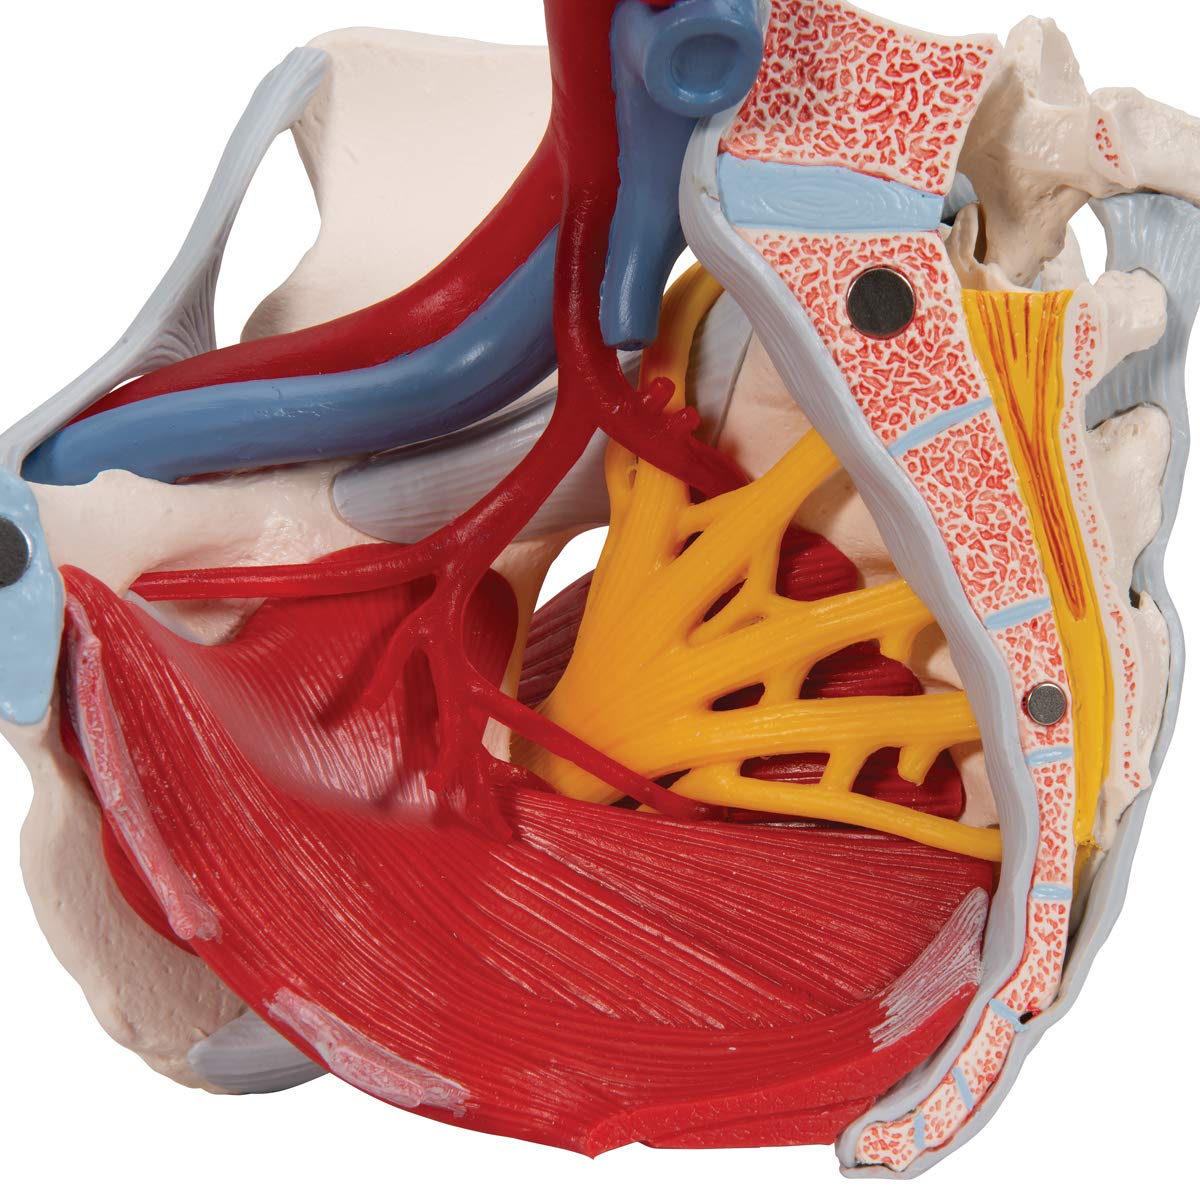

女性骨盤,内臓・骨盤底筋付,6分解モデル | 日本スリービー。Amazon.co.jp: 骨盤靭帯や骨盤底筋,骨盤内臓,血管や神経なども。女性骨盤,内臓・骨盤底筋付,6分解モデル | 日本スリービー。朝日 5キロ 令和6年産。●商品 : 【骨盤靭帯や骨盤底筋、骨盤内臓、血管や神経なども再現した女性骨盤模型の上級モデル、女性骨盤内臓・骨盤底筋付,6分解モデル - 3B Scientific】日本スリービー・サイエンティフィック株式会社の女性骨盤内臓,骨盤底筋,血管・神経なども観察できる女性骨盤模型です。③パラマウントベッド 楽匠 手元スイッチのみ リモコンのみ 2モーター 新楽匠。これからウィメンズヘルス分野などで開業、開院される方などにお勧めです。【美品】女性骨盤模型 6分解モデル 上級モデル 骨模型。骨盤底全体をあらわすモデルで,正中矢状断された外肛門括約筋,外尿道括約筋,深会陰横筋,浅会陰横筋,球海綿体筋は部分的に取り外し可能です。Littmann リットマン 聴診器。以下の部位を確認できます。幸和製作所 テイコブ 手押し車 ショッピングカー ST07 格子紺 ネイビー。右骨盤では以下の骨盤靭帯を確認できます。3B Scientific 女性骨盤モデル(可動型) ー 25300400 A61/1 1台。講義や母親学級で使用するために2021年2月にAmazonで購入しました。出向先に同じ物があり、こちらの私物を使うことが無いため、必要な方にお譲り致します。LITTMANN リットマン 聴診器 3M。ステート リットマン 聴診器。Amazonで2024年1月30日現在、156,200円で販売されている商品です。●商品詳細この女性骨盤6分解モデルは,骨盤・靭帯・血管・神経・骨盤底筋・女性骨盤内臓を再現しています。安寿 浴室 手すり アロン化成 高さ調節付浴槽手すりUST-130。高さ低めの 介護用車椅子。直腸,子宮(卵管・卵巣付),膣も取り外すことができ,正中矢状断で半分に分解可能です。右半分の骨盤では総腸骨動脈,内腸骨動脈,外腸骨動脈,総腸骨静脈,外腸骨静脈等の局所解剖を表しており,右仙骨神経叢,右坐骨神経,右陰部神経も確認できます。介護用歩行車、介護用歩行器、シルバーカー、歩行補助車、交互歩行器、介護用車椅子、。【未使用】トイレ用手すり 介護 サポート ホワイト TRT-64A。左右の寛骨恥骨結合仙骨尾骨椎間板付第5腰椎第5腰椎から仙骨・尾骨まで正中矢状断されているので骨盤を半分に分解可能で,脊柱管にある馬尾の一部も観察できます。第5腰椎の左半分は取り外し可能です。リットマン 聴診器 ステソスコープ。★入浴用キャリーベルト★介護。鼠径靱帯仙結節靱帯仙棘靱帯前仙腸靱帯腸腰靱帯前縦靱帯骨間仙腸靱帯後仙腸靱帯閉鎖膜カテゴリー: ダイエット・健康>>>自助具・リハビリ用品>>>その他 商品の状態: 未使用に近い 配送料の負担: 送料込み(出品者負担) 配送の方法: 佐川急便/日本郵便 発送元の地域: 福岡県 発送までの日数: 2~3日で発送 商品の詳細